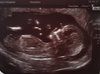

Hej dziewczyny właśnie do was dołączyłam mam termin na 2-6 stycznia